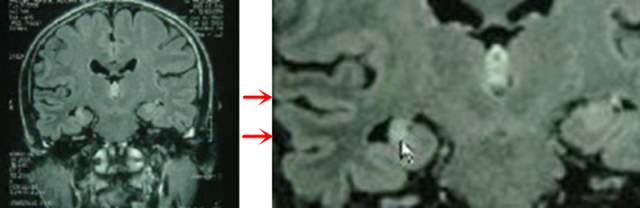

海马体积萎缩是神经元丢失在MRI上的反映,神经胶质增生及水肿导致海马T2WI信号增高。

2、间接征象—-侧脑室颞角扩大和海马头部浅沟消失。